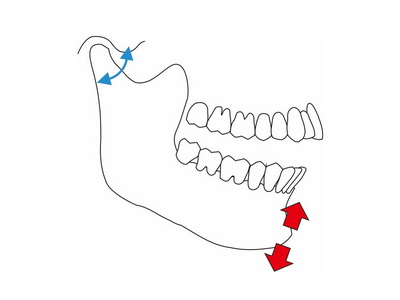

オトガイ誘導法は下顎頭を関節窩の後上方に誘導する (図2)

なお,オトガイ誘導法は強くオトガイを後方に押すと,ナソロジーで使用されるターミナルヒンジアキシス(最後退位)を求める方法になります

(図2)One hand push back

ナソロジーが流行った時は最後退位,また顎関節内障が流行した際には,Dowson法による前上方位がベスト言われていましたが.現在個人的には後方に押さず,患者の開閉口運動に合わせてオトガイを上下に動かすオトガイ誘導法(図3)を使用し,スムーズな顎運動の確認や,習慣性閉口位で咬合接触時に下顎の偏位が生じていないかを確認していますが,顆頭安定位を求める方法と考えますが,あくまでも咬合の安定性を確認する診査なので咬合採得では使用していません.

(図3)オトガイ誘導法